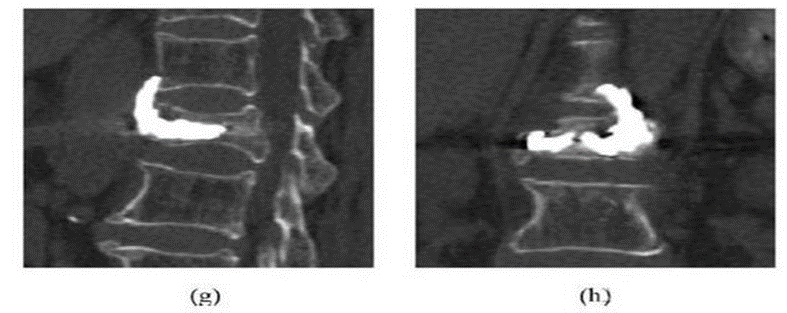

椎体定位:正侧位脊柱呈标准正位:左右两侧椎弓根投影对称,棘突投影位于椎体正中央进针点:椎弓根外侧缘中点略偏足侧的体表投影向外旁开1.5-2cm。进针方向:向矢状面成10°-15°

侧位:针尖至椎弓根的1/2;正位:针尖位于椎弓根影的中线处侧位:针尖至椎体后缘;正位:针尖位于椎弓根的内侧缘侧位:针尖至椎体前中1/3交界处;正位:针尖位于椎体中线略偏对侧

骨钻建立通道:钻头尖到达椎体前1/3处钻动骨钻时可闻及钻动骨质的沙沙声用带芯的骨水泥填充器探测,证实椎体前缘皮质未破

放入可扩张球囊,确保球囊位于椎体内(扩张前透视)扩张球囊:先加入2ml左右造影剂,同时时观察压力表,后每次增加造影剂0.5ml,透视至椎体扩张到满意程度,球囊系统压力控制在15个大气压左右。

注意:扩张球囊时对侧骨钻要抽出

球囊停止加压:A.终板抬高,达到治疗时B.球囊靠近骨皮质或终板时C.对比剂已注入4MLD.扩张压力已达到15个大气压左右